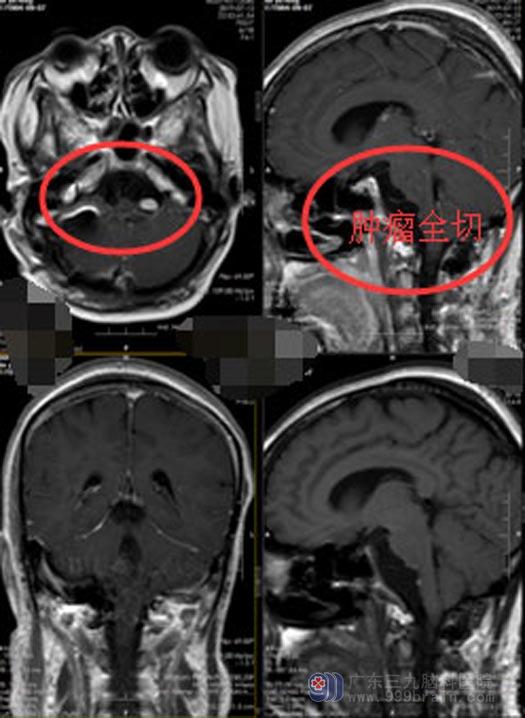

充分的术前准备后,显微镜下为林女士施行“右侧改良远外侧入路脑干侧前方桥延池前区占位病变切除术+硬脑膜修补术+颅骨成型术”,术中小心避开椎动脉,充分暴露视野后,发现病变区域包裹椎动脉、后组颅神经及延髓,仔细切除病灶,不仅切除了右侧肿瘤及脑干前方肿瘤,还完全切除了左侧肿瘤,达到了肿瘤全切。

手术顺利,麻醉清醒后林女士生命体征平稳,对答切题,视力视野正常,四肢活动自如,未出现明显神经功能障碍。复查核磁共振显示肿瘤全切,病理报告示:表皮样囊肿。